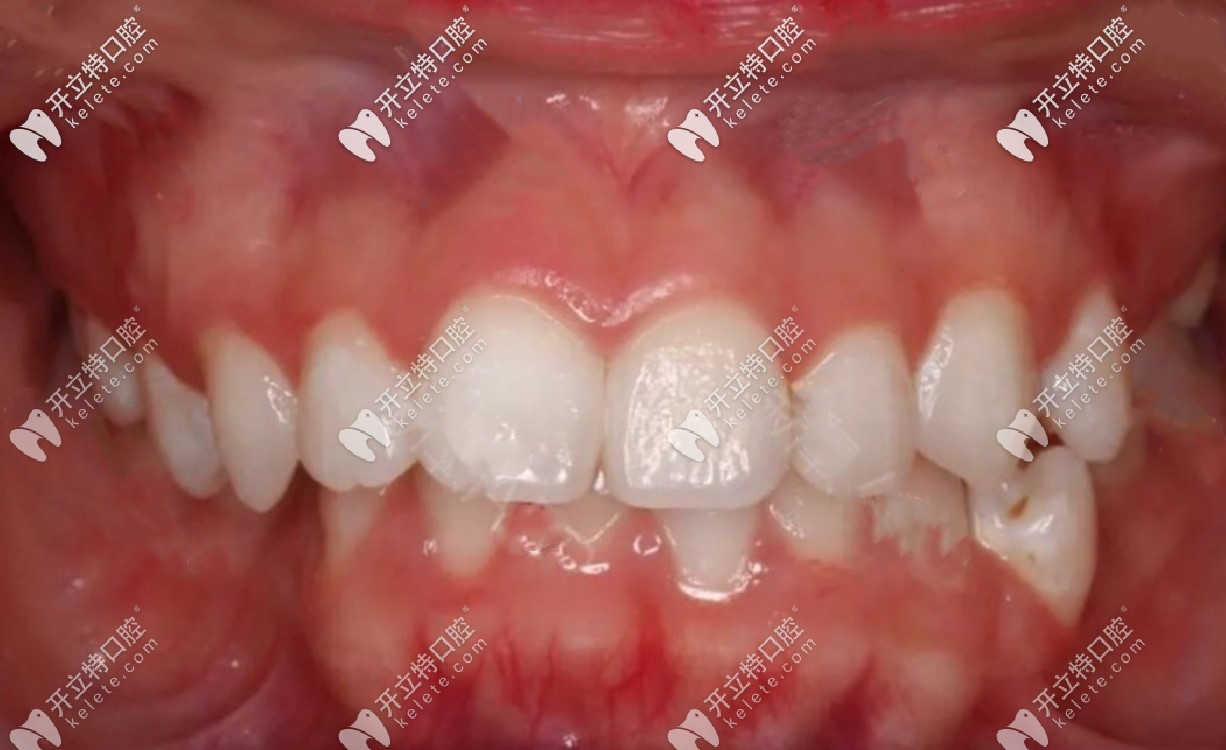

矯正前牙齒照片▼

矯正前牙齒照片